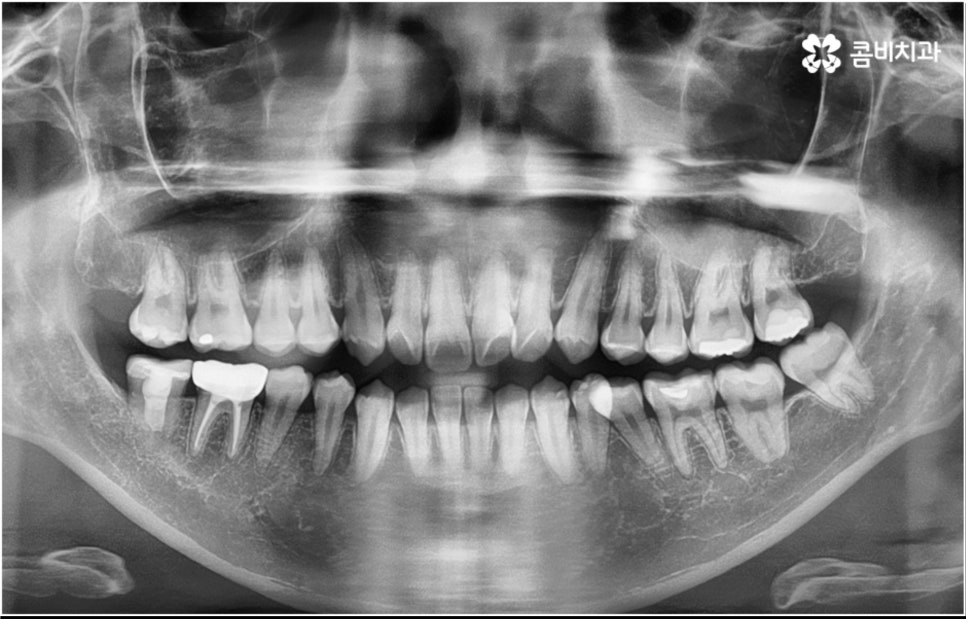

3D CT 등 정밀 검진 기계를 통해 꼼꼼하게 검진을 한 후 환자분들의 부정교합의 종류 및 정도 등에 따라 각자에게 맞는 교정 치료 계획을 수립하게 되는데, 내부 공간이 얼마나 있는지에 따라 발치가 필요한지 아닌지 여부도 달라지고 또 같은 부정교합이라고 해도 사람마다 잇몸 건강이나 치근 상태 등에 따라 잇몸뼈가 벌어지면서 치아가 이동하는 속도, 치아가 자리잡는 양상 등도 모두 달라지기 때문에 성인 치아교정 기간 총 소요 시간은 모두 달라질 수 밖에 없을 거예요.

하지만 부정교합의 정도가 심하거나 골격적 문제를 바로잡아 주어야 하는 경우는 전체 교정을 진행해야 하기 때문에 (환자분들마다 다르지만) 평균적으로 18~36개월 정도의 성인 치아교정 기간 이 소요되며, 중장년 성인분들 중에 잇몸 질환 등으로 구강 건강이 약해져 있는 분들의 경우에는 더욱 환자분들의 상황에 맞게 필요한 치료를 병행하면서 무리하지 않은 진행을 해야 하기 때문에 전체 기간이 좀 더 늘어날 수 있어요.

특히 부정교합의 종류 중에 청소년기보다 더 어릴 때 1차적으로 골격적인 부분을 조절하면서 보다 균형잡힌 성장을 유도하는 것이 필요한 케이스도 있으니 46세 정도의 유치열기 또는 78세 정도의 혼합치열기 초반 무렵부터 치과에 주기적으로 방문하여 검진 및 스케일링 등 치아 상태에 대해 전반적인 점검도 받으면서 혹시 교정 치료가 필요하지 않은지 여부도 확인해 보면 좋을 거예요.